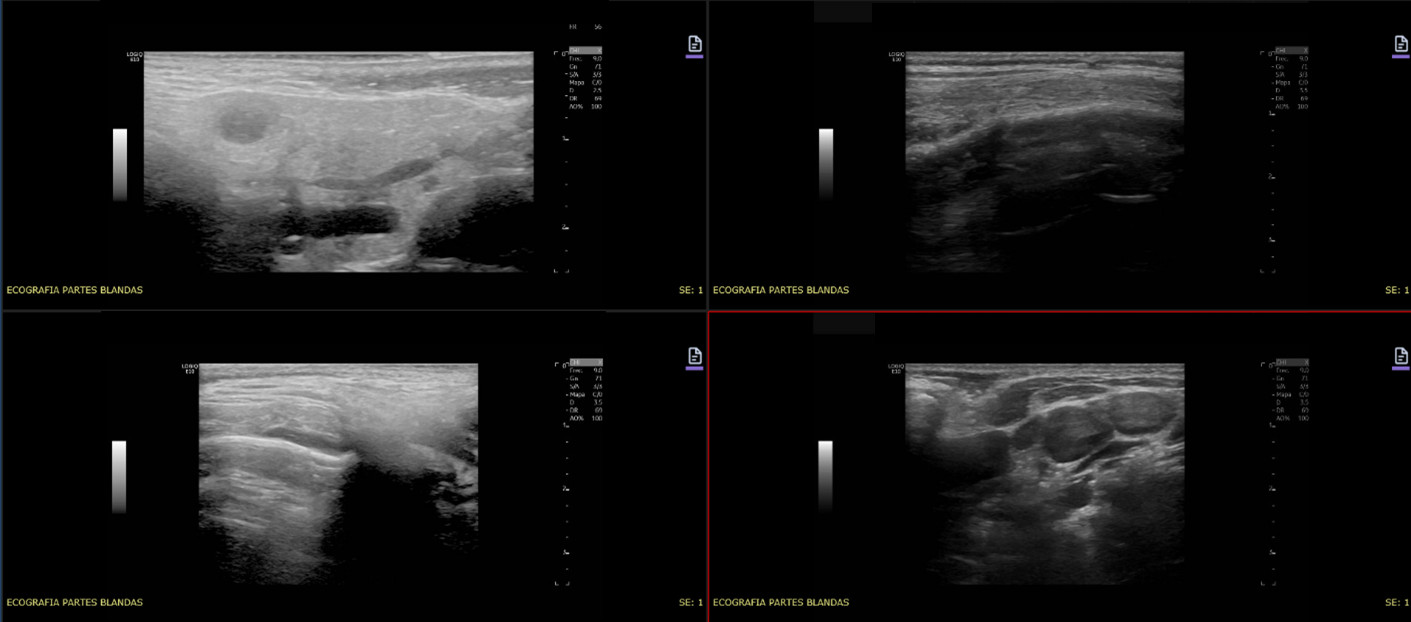

Varón de 8 años, como único antecedente OMA en 2023 con buena respuesta a la antibioterapia. Valorado en su centro de salud por otalgia izquierda y rinorrea de 24 horas de evolución, afebril. Se inicia tratamiento con ibuprofeno. Se revalora a las 48 horas por persistencia del dolor. En la exploración destaca tumefacción facial discreta dolorosa a nivel del arco cigomático y dolor a la manipulación articular temporomandibular con leve dificultad para su apertura. Se deriva a urgencias para valoración, donde se realiza analítica con elevación de reactantes de fase aguda y ecografía en la que se observa pequeña colección anecogénica subperióstica de 15 x 3 mm entre el músculo temporal y el hueso temporal izquierdo (Figura 1). Ante sospecha clínica, se inicia antibioterapia intravenosa e ingresa, con buena evolución posterior y resolución del cuadro, por lo que no se realizan más pruebas complementarias. Se realiza seguimiento posterior por Otorrinolaringología con controles normales.

Figura 1. Ecografía